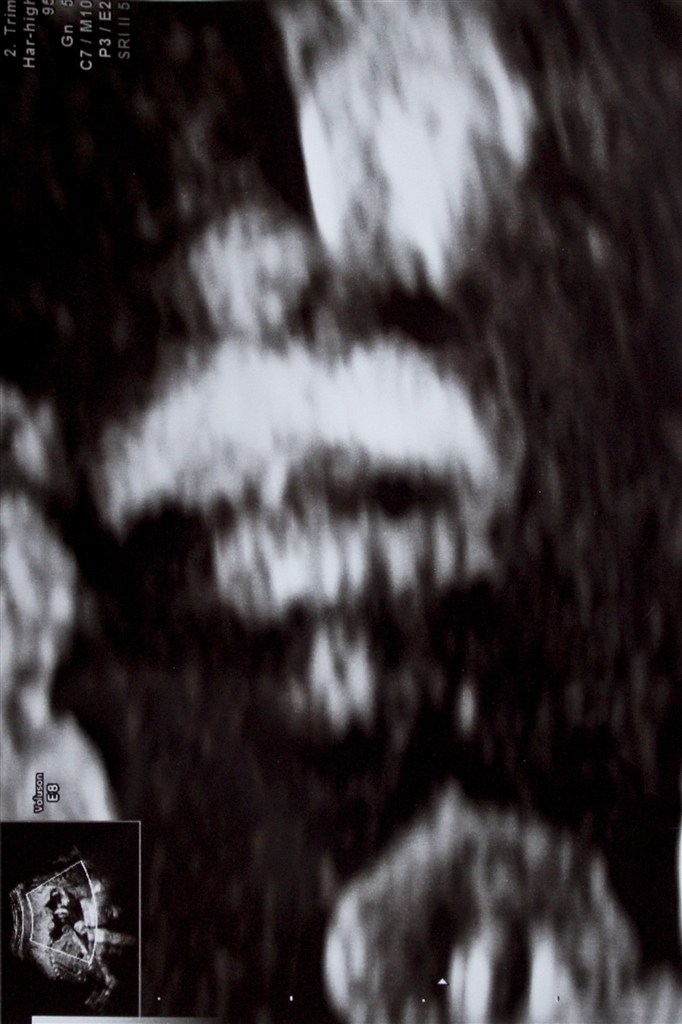

Billede nr. 3: Closeup af hendes over- og underlæbe samt næse.

Desuden ligner hun samtlige kvinder på både sin mødrende og fædrende side, for hun var så snotstædig at hun nægtede at vende sig om, på trods af jordemoderens skubben og masen. Først da jordemoderen opgav, vendte hun sig da lidt, så vi aller nådigst fik lov at se hende i profil.